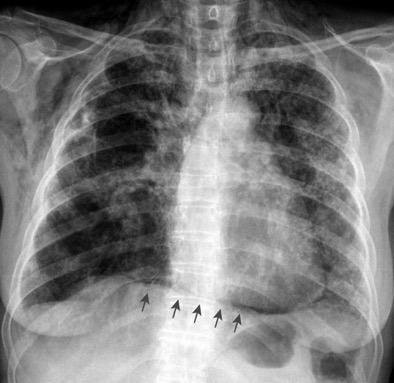

Tromboembolismo pulmonar Diafragma elevado 20%

Atelectasia crónica de LLI en paciente con enfermedad neuromuscular.

Los vasos aparecen paralelos en el lado derecho.

Dandawat.N et al. Diaphragmatic paralysis in COVID-19: a rare cause of postacute sequelae of COVID-19 dyspnoea . MJ